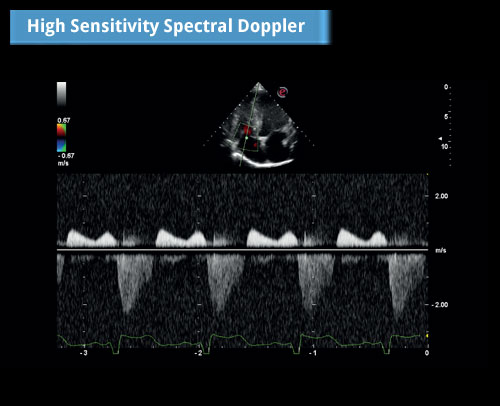

Spektrální doppler s vysokou citlivostí: Střední regurgitace trikuspidální chlopně - CW dopplerovský signál.